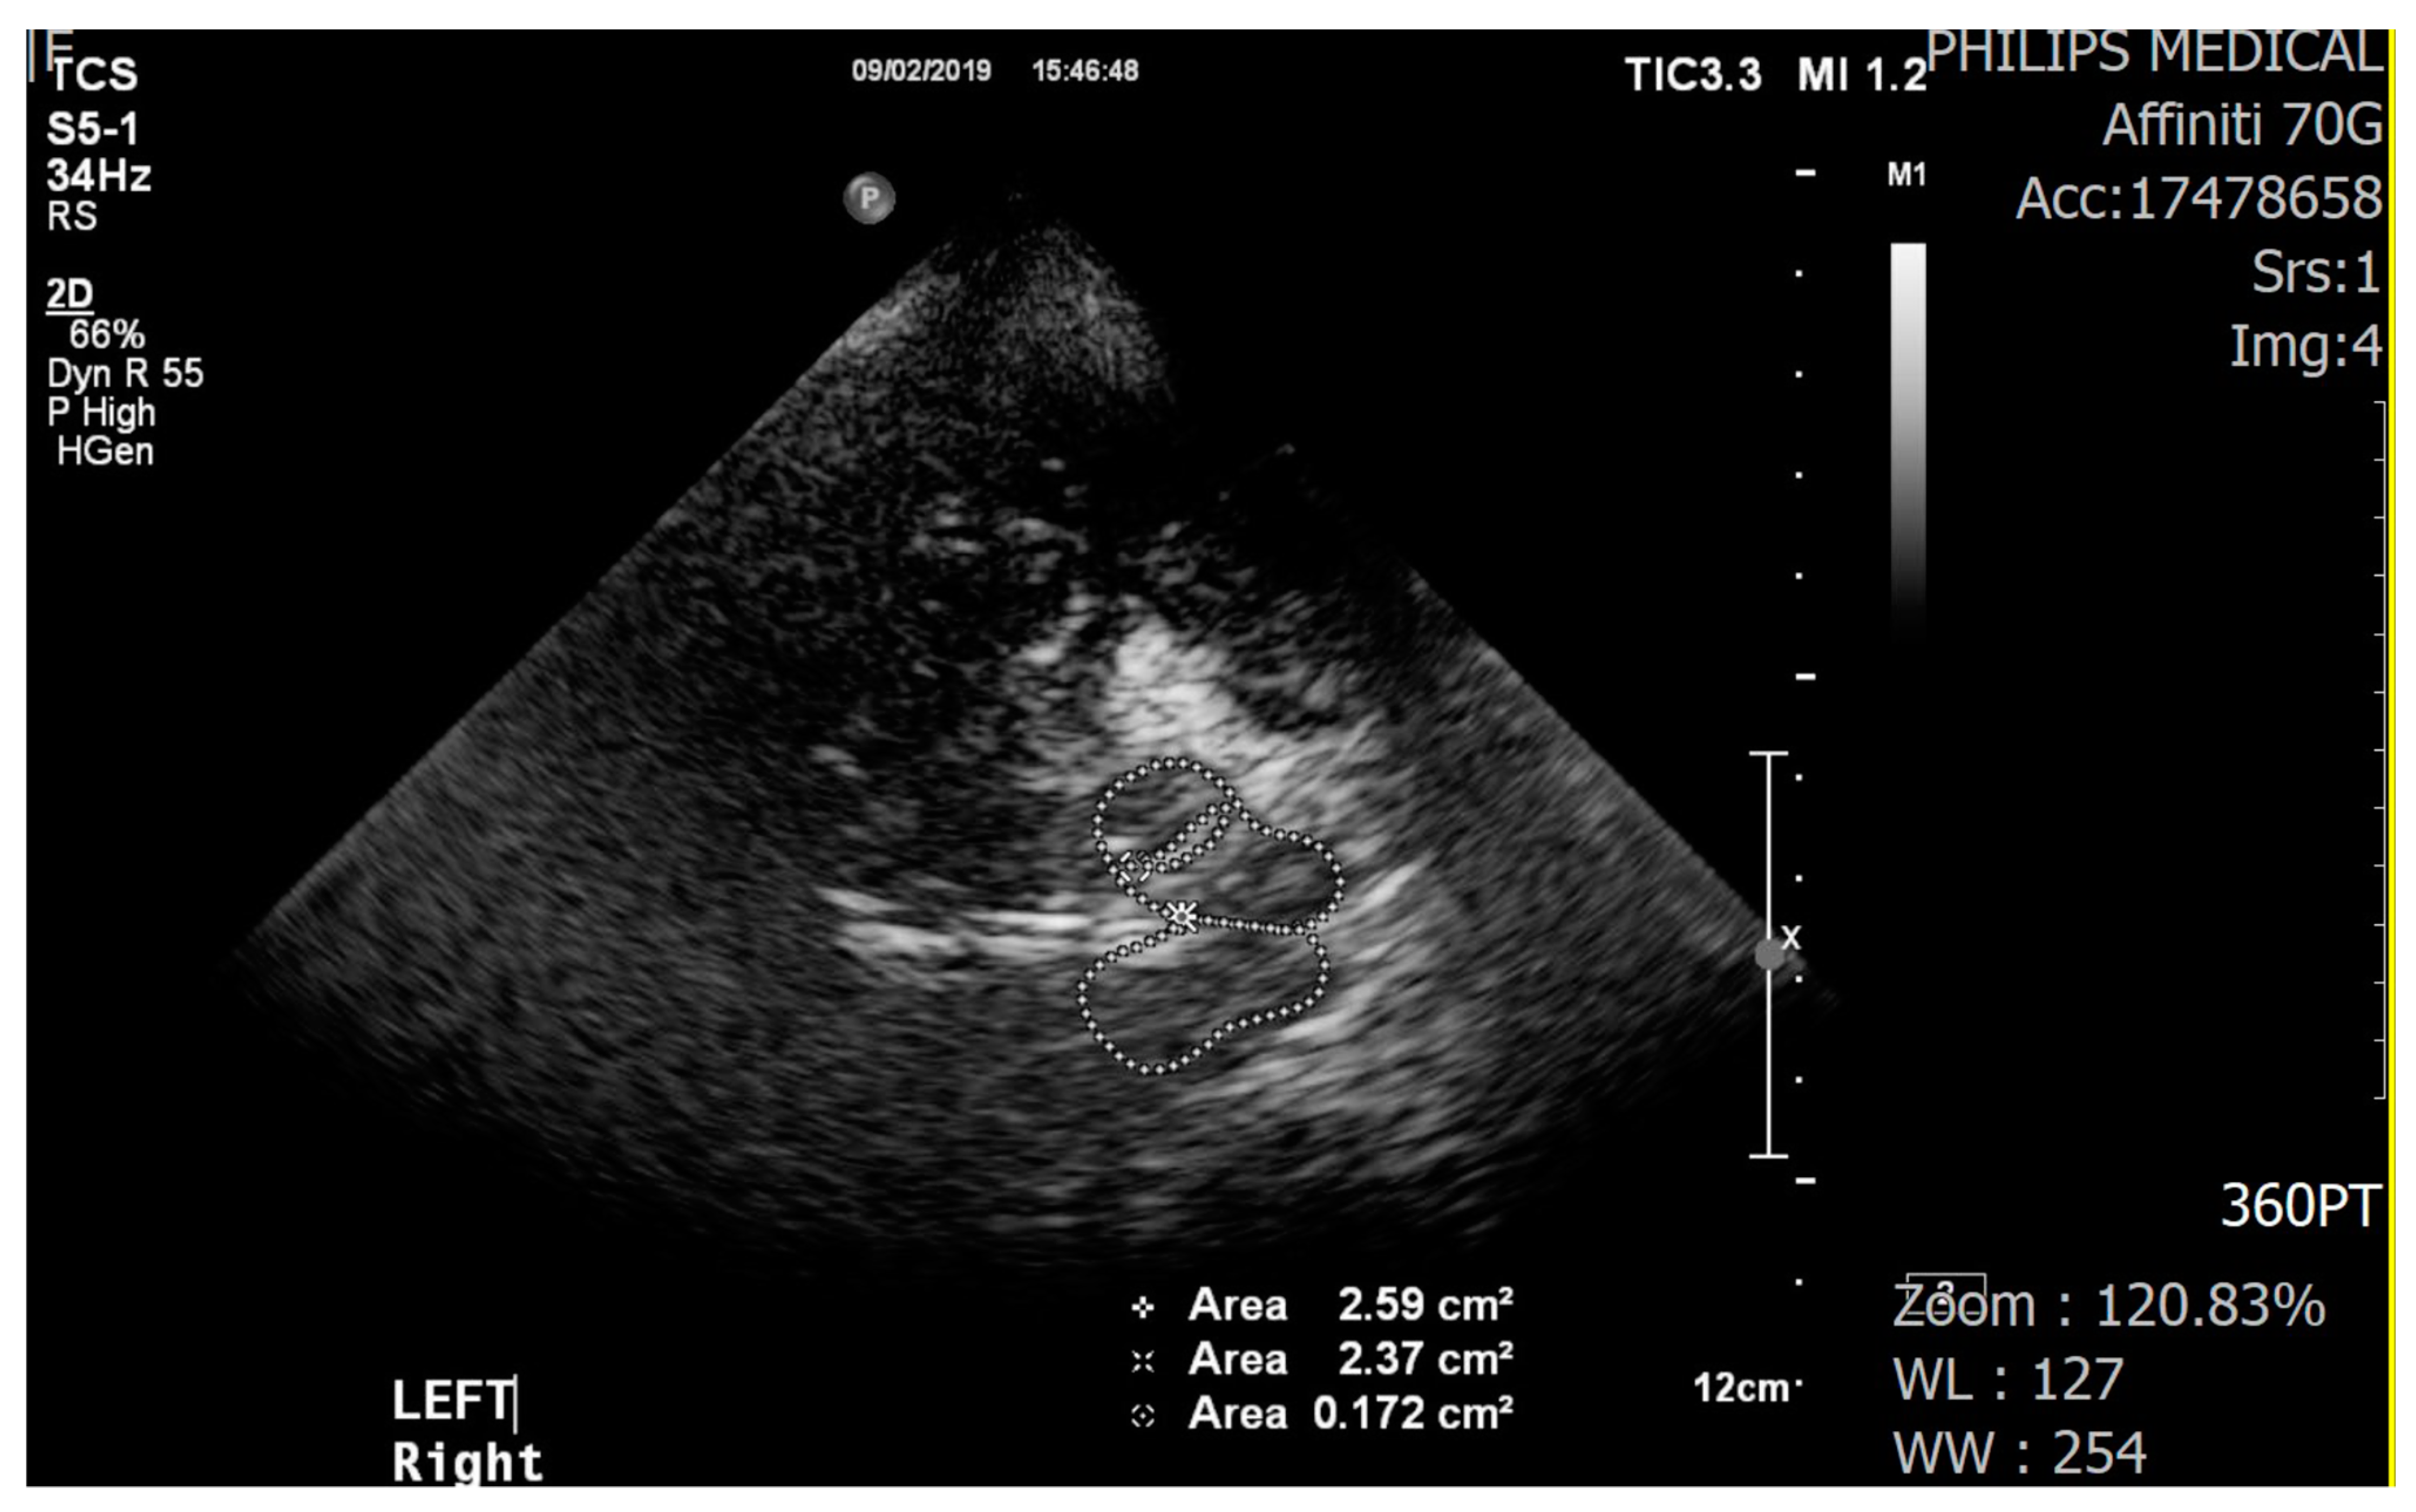

We used a color-coded duplex ultrasound system equipped with a 2.0–2.5 MHz phased array transducer (HDI 5000, SonoCT: Philips). Using a low frequency of 2.0–2.5 MHz makes it easier for ultrasound to pass through the temporal bone in the skull. Ultrasound parameters included a penetration depth of 16 cm and a dynamic range of 45–50 dB. The examination with the TCS probe was performed through the preauricular acoustic bone window, on both the right and left sides. The visualization of the target structures may depend on the quality of the temporal acoustic bone window. The SN was identified as a tie-shaped echogenic signal within the butterfly-shaped mesencephalic brainstem. To check hyperechogenicity, the sonographer marked areas manually but measurements were performed automatically (Figure 1). TCS results were examined by a well-trained sonographer who was not informed about the participants’ group allocation. All TCS images were stored and evaluated offline by an experienced neurologist who had no information about the participants’ group allocation.

Figure 1.

Transcranial sonography images of the midbrain (butterfly-shaped, left and right) and hyperechogenicity of the substantia nigra (encircled by the dotted line, inside the midbrain).